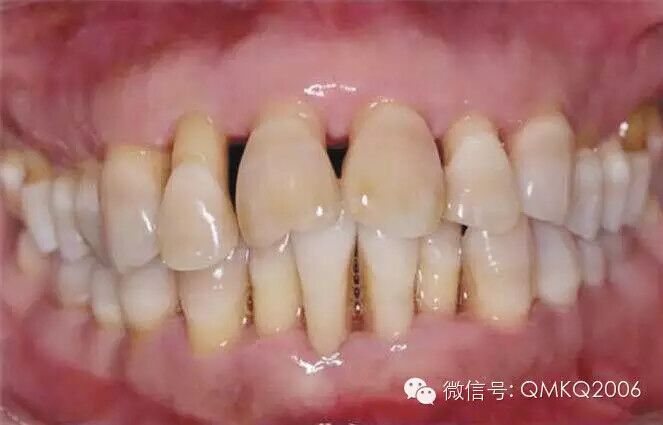

誤區(qū)4 齙牙或牙列不齊,尋求7天快速矯正法

所謂的美容冠快速矯正,號(hào)稱新興美齒技術(shù),本質(zhì)還是把牙磨小后做烤瓷冠,為了美觀卻損害了牙齒健康。改變健康牙齒的排列,正確方案就是戴矯正器,時(shí)間一般為兩年左右。牙齒的生理性移動(dòng)是一個(gè)緩慢的過程,矯正必須付出時(shí)間代價(jià),沒有捷徑可走。